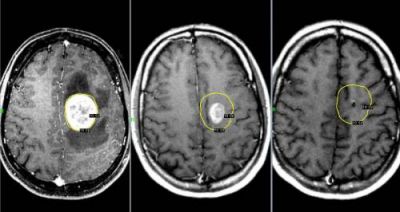

Опухоль мозга

Данное новообразование появляется в тканях мозга и может быть как злокачественным, так и доброкачественным. Последнее можно вылечить без хирургического вмешательства. Злокачественная опухоль растет очень быстро и дает метастазы. Поэтому лечению заболевание поддается с трудом, особенно на поздних стадиях.

При данном заболевании боль ощущается постоянно, а во время движения только усиливается. Самые сильные боли бывают в утреннее и ночное время вследствие накопления избыточной жидкости в тканях. Характер боли — давящий, пульсирующий.

Опухоли мозга

Злокачественные опухоли характеризуются быстрым прорастанием в другие ткани с их последующей трансформацией. При этом метастазы могут наблюдаться сразу в нескольких участках мозга.

Такие опухоли плохо лечатся, а на поздних стадиях их развития спасти человека практически невозможно.

Клиническая картина

Характер болевых ощущений — постоянный, по мере развития заболевания продолжительность приступов увеличивается. Когда человек двигается, болевые ощущения усиливаются. Сначала они локализуются в области опухоли, потом, по мере увеличения внутричерепного давления, переходят в лобную и затылочную часть. Наиболее сильный дискомфорт наблюдается в ночное и утреннее время из-за скопления жидкости. Вены не справляются с оттоком крови, поэтому к болям прибавляются отёчность и застои. Боли давящие, распирающие, пульсирующие.

К головным болям затем добавляется рвота. При физической нагрузке или кашле болевые ощущения усиливаются, появляется двоение в глазах, временами исчезает зрение. Голова кружится, у пациента нарушается координация движений. Могут неметь конечности, ослабляется тонус мышц.

Иногда бывают эпилептические припадки, путается сознание.

Вмешательство врача

Необходима помощь терапевта, нейрохирурга, онколога, онколога-радиолога.

Диагностирование

Для диагностики используется МРТ мозга, ПЭТ, КТ мозга, ангиография и другие методы.